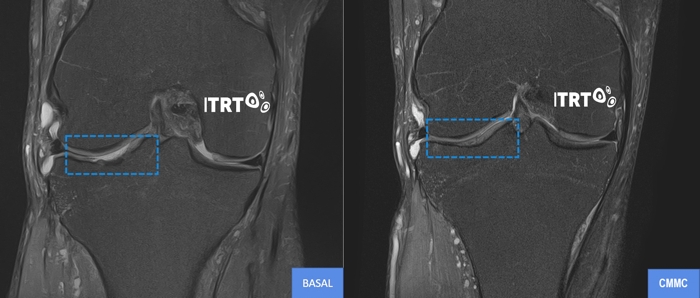

La teràpia desenvolupada per ITRT sí que ha demostrat en assaigs clínics controlats mitjançant Ressonància Magnètica d'alta resolució (T2Mapping), tenir la capacitat de regenerar el cartílag de les articulacions i evitar la necessitat de costoses i molestes pròtesi.

Els assaigs clínics realitzats han demostrat que amb una sola dosi de cèl·lules mare mesenquimals cultivades (CMMC) és suficient per deslligar el poder regeneratiu i curar la lesió. La millora de el dolor s'experimenta de forma gairebé immediata i va evolucionant juntament amb la funcionalitat durant els 3 primers mesos.